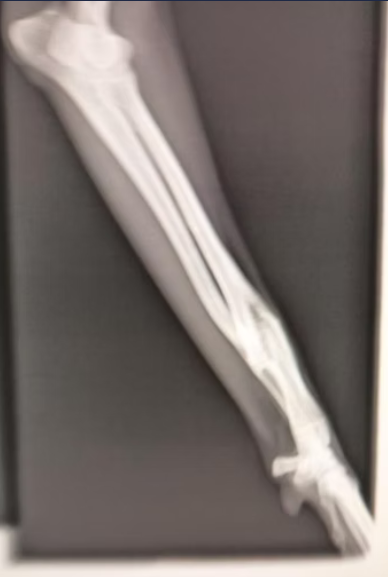

Ich bin Electra. Wie viele andere Hunde hier, bin ich eine ausrangierte Jagdhündin. Leider war mein Vorderlauf gebrochen. Dies ist aber problemlos verheilt und es muss auch nicht operiert werden. Trotzdem war dies wohl Grund genug mich einfach auf die Strasse zu setzen.